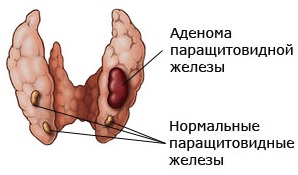

Иллюстрации и схемы по остеопорозу и паращитовидной железе